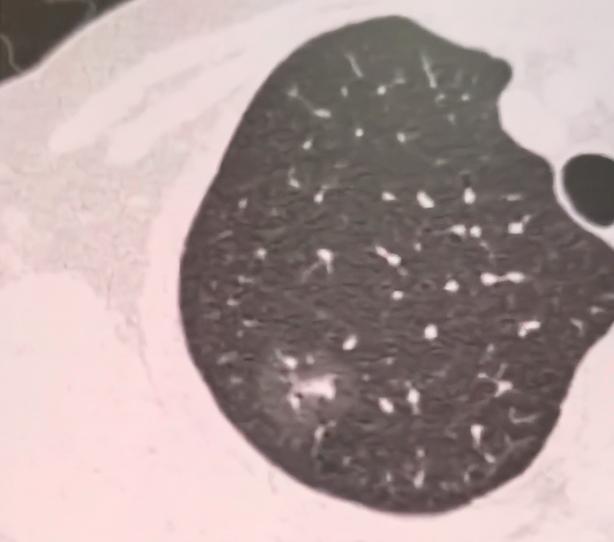

体检查出肺结节,到底多大才要做手术?我的临床原则讲给您听......最近碰到很多患者,体检查出肺结节后,一听说结节快到8mm,就慌得不行,觉得必须马上做手术。

我在临床工作这么多年,一直有个明确的原则:结节的大小,从来都不是决定要不要做手术的唯一标准。很多人觉得8毫米是“临界值”,到了这个尺寸就必须切,这其实是个误区。

就拿我接诊过的患者来说,有的结节已经长到1公分,甚至2公分,但是通过半年、一年的定期复查,发现它一点变化都没有,既没变大,也没出现形态异常,这种情况下,我们根本不用急于手术,继续定期观察就好。

反过来也一样,有些患者的结节只有6毫米,不算大,但每次复查都能发现它在慢慢增长,哪怕没到8毫米的“标准线”,我也会建议他及时手术干预。大家一定要记住,结节的增长,才是我们最需要警惕的信号。